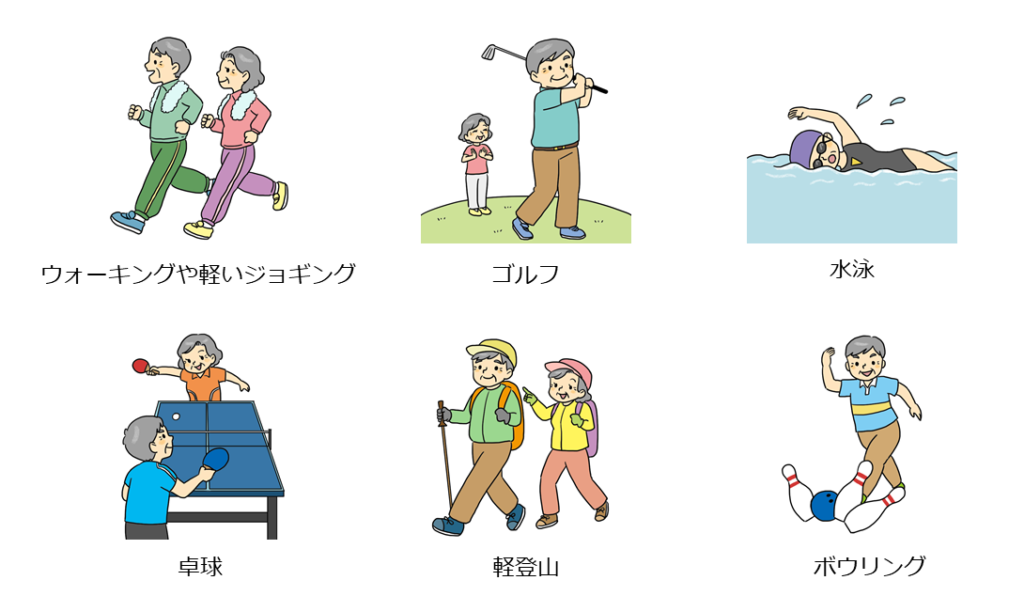

「人工股関節置換術の術後にスポーツをしても大丈夫でしょうか?」とよく聞かれます。ウォーキングや軽いジョギング、ゴルフ・水泳・卓球・登山・ボウリングなどは全く問題ないでしょう。